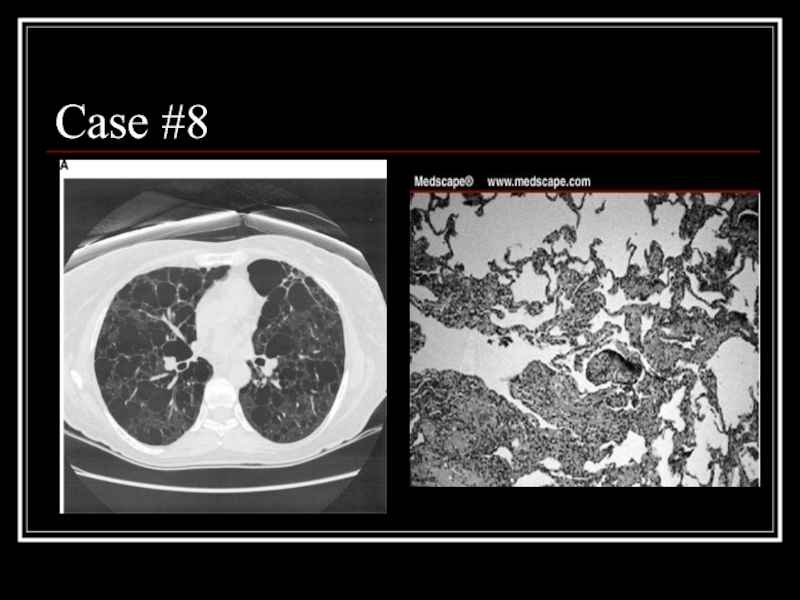

Слайд 33Case #8

Слайд 34Answer: LAM

CT: Diffuse parenchymal cysts

Path: nodular proliferation of smooth muscle (LAM)

cells replacing the lung parenchyma and jutting into air spaces